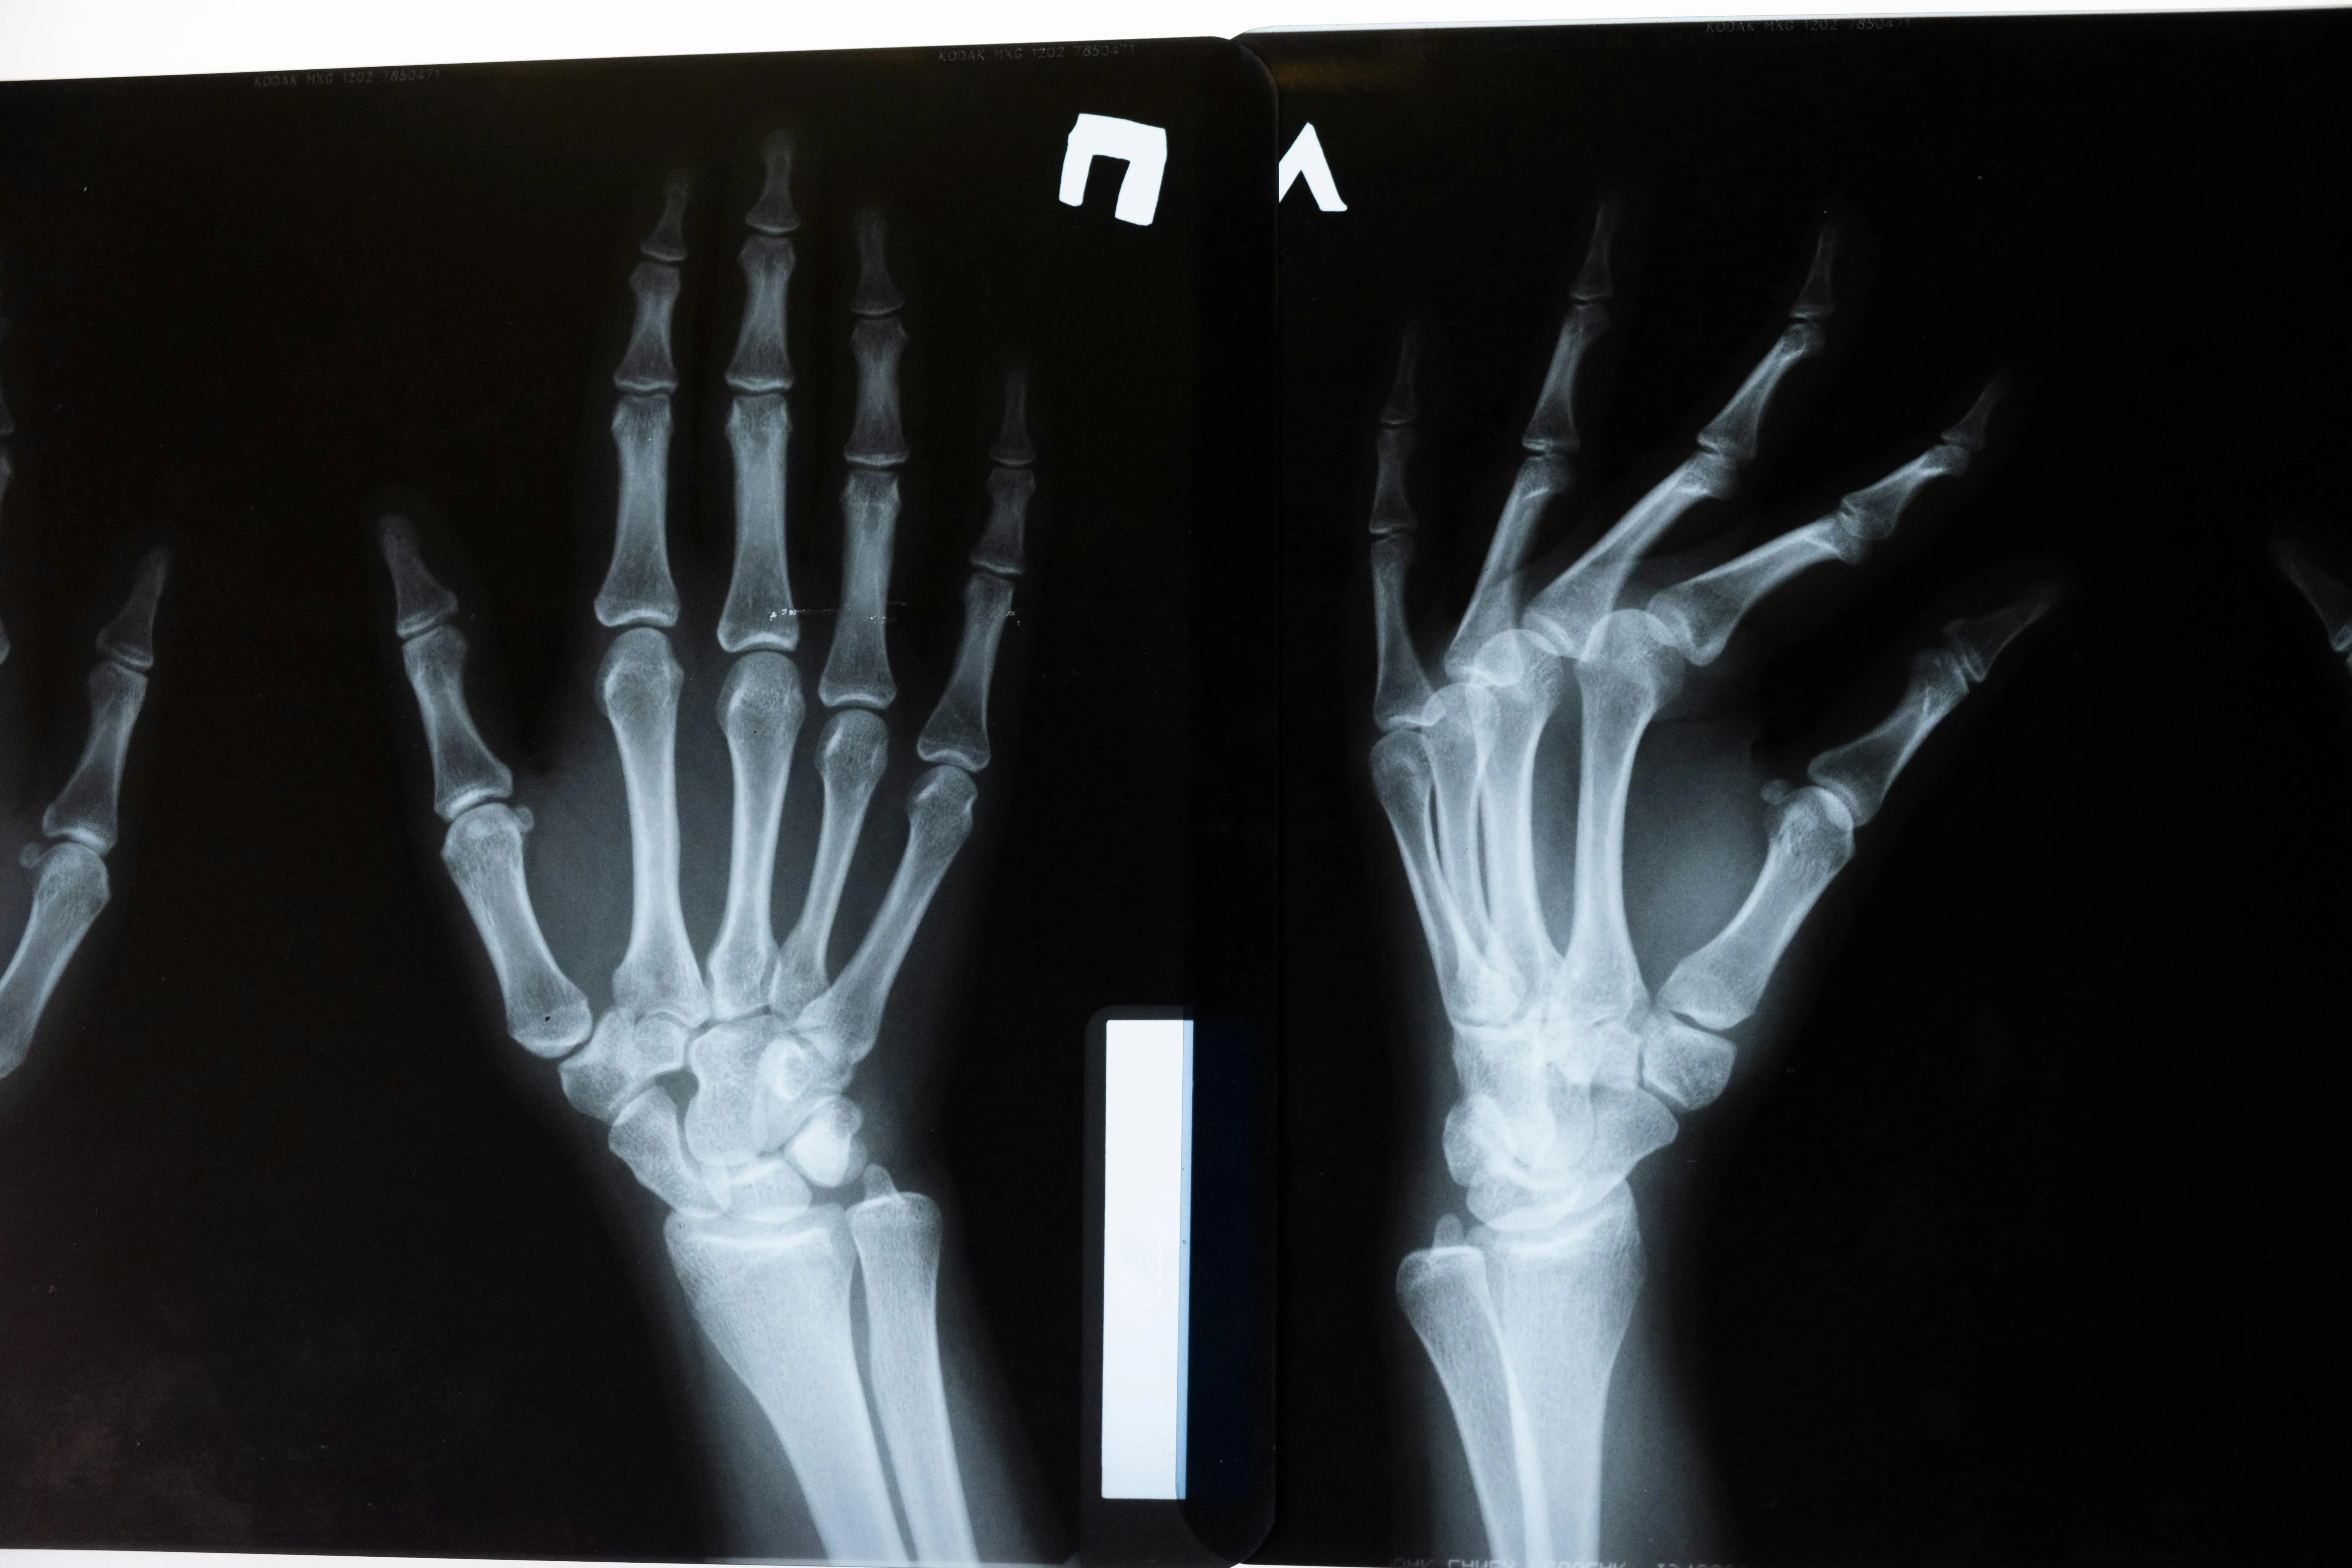

콘드로이친(Chondroitin)은 우리 몸의 연골과 결합조직 속에 자연적으로 존재하는 성분으로

관절 사이에서 충격을 흡수하고 마찰을 줄여주는 역할을 합니다.

나이가 들면서 콘드로이친이 점점 감소하면 관절이 뻣뻣해지고 통증이 생길 수 있다고 합니다.

콘드로이친 효능 2 – 연골 보호 및 재생 도움

콘드로이친은 단순히 통증을 완화하는 것에 그치지 않고,

-연골 세포의 손상을 줄이고 재생을 돕는 역할도 합니다.-

콘드로이친 효능 3 – 관절 윤활 및 유연성 개선

콘드로이친은 관절 속의 윤활 작용을 촉진해 마찰을 줄여주는 역할을 합니다.

실제로 콘드로이친은 관절액의 점도를 높여 유연성을 개선하는 효과가 있다고 합니다.